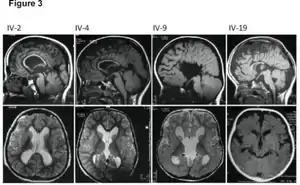

MRI images showing megalencephaly in four family members who all have unusually large skulls (the family is affected by an autosomal recessive syndrome caused by a KIF7 mutation that induces multiple epiphyseal dysplasia)[1]